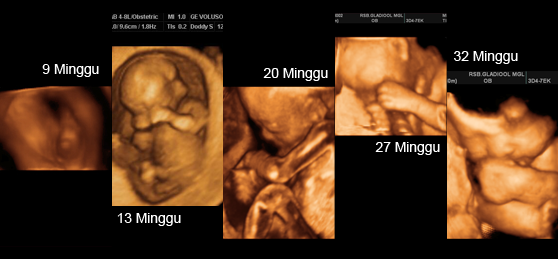

Perkembangan Janin Usia 28 Minggu - Bidanku.com Tahapan Perkembangan Janin: Minggu ke-28 Perkembangan Janin 28 Minggu Kehamilan • Hello Sehat PERKEMBANGAN JANIN 7 BULAN (25 - 28 MINGGU) - YouTube Informasi Perkembangan Janin 28 Minggu dan Perubahan Tubuh Ibu - Alodokter Kehamilan Berusia 28 Minggu: Apa yang Diharapkan Terjadi Perkembangan Janin dan Ibu Hamil Minggu ke-28 Perkembangan Bayi Dalam Kandungan Hamil 28 Minggu Begini Perkembangan Janin pada Usia 28 Minggu Perkembangan Janin 28 Minggu Kehamilan-Perubahan Ibu & Bayi Kondisi Bayi Prematur yang Lahir pada Usia Kandungan 28, 31, 33, dan 36 Minggu - Ibupedia Mukjizat Allah! Bayi Prematur 28 Minggu Ini Bisa Hidup Normal - Tribun Jateng Perkembangan fetus - hamil 28 minggu - BabyCenter Hasil USG 4D 28 minggu - YouTube Perkembangan janin 28 minggu, panduan kehamilan minggu ke minggu | theAsianparent Indonesia Perkembangan Bayi Dalam Kandungan Hamil 28 Minggu Perkembangan Pesat Janin Tiap Minggu Selama Trimester Tiga Hamil 28 Minggu dan 10 Komplikasi yang Sering Dirasakan Ibu Hamil Fase Penting Dalam Perkembangan Janin 28 Minggu - Mamapapa.id % Fase Penting Dalam Perkembangan Janin 28 Minggu - Mamapapa.id % Ultrasound fetus – 6 bulan - BabyCenter Hamil 28 Minggu: Saatnya Mulai Rutin Melakukan Senam KegelElla | MamiBuy Foto Perkembangan Bayi Kembar di Dalam Rahim Ibu Hamil - kumparan.com Perkembangan Janin 28 Minggu Kehamilan • Hello Sehat Perkembangan Janin Usia 7 Bulan (28 Minggu) dan Bentuk dalam Kandungan Mukjizat Allah! Bayi Prematur 28 Minggu Ini Bisa Hidup Normal - Tribun Jateng 10 Cara Mudah Prediksi Jenis Kelamin Bayi (No. 9 Paling Mudah) 28 minggu - IbuHamil.com Perkembangan Janin Saat Hamil 28 Minggu yang Harus Moms Ketahui - Inspirasi Shopee Arti Janin Aktif Bergerak Sebelah Kanan - Alodokter Perkembangan Janin 7 Bulan (28 Minggu) - Hamil.co.id Kehamilan dan Perkembangan Janin Ukuran 27 s/d 28 Minggu - YouTube Betul ke 29 minggu? Saya terus ditahan wad’ - Ibu lahir bayi besar tapak tangan (800 gram) - The Reporter Perkembangan janin kembar - Kumpulan foto janin dari minggu ke minggu | theAsianparent Indonesia Bayi Umur 28 Hari Sudah Satu Minggu Belum BAB - Tribun Lampung 5. tumbang hasil konsepsi Risiko bersalin pramatang | Harian Metro Bayi Pramatang - PORTAL MyHEALTH Mukjizat Allah! Bayi Prematur 28 Minggu Ini Bisa Hidup Normal - Tribun Jateng 25 Gambar Pembentukan Bayi Dalam Kandungan Setelah 12 Tahun Dirakam. Menakjubkan! Faktor Penghambat Kenaikan Berat Badan Janin - Bestmom.id | Info Kehamilan, Melahirkan, Parenting Lakukan USG Saat Trimester Kedua, Mama Bisa Tahu 6 Hal Penting Ini | Popmama.com usia janin 28 minggu, BB debay 1700, kegedean banget kah? - IbuHamil.com Ukuran Berat Janin Dalam Kandungan | kumpulan materi pelajaran dan contoh soal 5 Usia Kehamilan 28 Minggu Janin Kerap Sungsang? Tenang, Tidak Berbahaya, Ini Penjelasannya! - Serambi Indonesia Kedudukan bayi dalam kandungan - 7 cara meneka kedudukan bayi | theAsianparent Malaysia Mama Lepaskan Aira Ya Sayang. Jumpa Mama Di Syurga… " Bikin Gemas! Penasaran Nggak Moms Posisi Janin dalam Kandungan? Fasa Perkembangan Bayi Dalam Kandungan, Bulan Ke Bulan Mama Lepaskan Aira Ya Sayang. Jumpa Mama Di Syurga… " Inilah 6 Faktor Penyebab Bayi Sungsang Perkembangan janin usia 28 minggu | LuviZhea Perkembangan fetus - hamil 28 minggu - BabyCenter 4 Fakta Unik Perkembangan Mata Bayi Saat di Kandungan EVA EMILY Clinic - Services | Facebook Bayi Melintang Tidak Sama Dengan Bayi Songsang”- Pakar O&G Jelas Apa Itu ‘Transverse Lie’ Gerakan Janin Dalam Perut, Mana yang Wajar dan Mana yang Berbahaya? - Mamapapa.id % MASA EMBRIOGENIK DAN MASA JANIN - ppt download Fase Penting Dalam Perkembangan Janin 28 Minggu - Mamapapa.id % Perkembangan Janin Usia 28 Minggu - Bidanku.com GERAKAN JANIN 7 BULAN 28-30 minggu - YouTube Perkembangan Janin 28 Minggu - Permulaan Trimester Ketiga | theAsianparent Malaysia Pergerakan Bayi Dalam Kandungan Yang Ibu Hamil Patut Tahu (Lengkap) | theAsianparent Malaysia Perkembangan Janin 29 Minggu, Si Kecil Semakin Aktif! - Mamapapa.id Bikin Gemas! Penasaran Nggak Moms Posisi Janin dalam Kandungan? 28 minggu - IbuHamil.com Nur Lydia hanya dapat sentuh bayi 2 bulan selepas melahirkan; bayinya seberat 680g sahaja! - BERITA MediaCorp Gawat janin - Gejala, penyebab, dan mengobati – Alodokter Pertumbuhan dan Perkembangan Hasil Konsepsi - ppt download AufaZanKi: ~trimester ketiga kehamilan~ Perkembangan Janin Bayi dalam Kandungan usia 1-40 minggu | dr. Adi SpOG Kehamilan Berusia 29 Minggu: Apa yang Diharapkan Terjadi Perkembangan bayi anda pada usia 1 bulan - BabyCenter Nur Lydia hanya dapat sentuh bayi 2 bulan selepas melahirkan; bayinya seberat 680g sahaja! - BERITA MediaCorp Imbasan 3D bergantung ‘kerjasama’ bayi | Harian Metro 14 JANIN USIA 7 BULAN LAHIR Bayi Lahir Prematur Lebih Baik di Usia 7 Bulan daripada 8 Bulan, Benarkah? Perkembangan Janin Usia 28 Minggu - Bidanku.com Perkembangan Janin 28 Minggu - Permulaan Trimester Ketiga | theAsianparent Malaysia Air ketuban berlebihan | Harian Metro Kehamilan Berusia 25 Minggu: Apa yang Diharapkan Terjadi Ini Berat Badan Bayi yang Normal Saat Lahir Kelahiran Prematur - Gejala, penyebab dan mengobati - Alodokter Fakta Kehamilan Trimester Ketiga yang Harusi Ibu Hamil Tahu | Popmama.com Cara Cek Perkembangan Janin dari Gerakan dan Jenis Tendangan - Tirto.ID Tiga Hal yang Jarang Orang Ketahui jika Ibu Hamil Lakukan USG 4D - Halaman all - Tribun Jabar Inilah Penyebab Bayi Terlilit Tali Pusar - Alodokter Kehamilan Berusia 31 Minggu: Apa yang Diharapkan Terjadi Fasa Perkembangan Bayi Dalam Kandungan, Bulan Ke Bulan Kelahiran pramatang - BabyCenter Moms, Ternyata Begini Lho Posisi Bayi Selama di dalam Kandungan 6 Penyebab Bayi Lahir Dengan Berat Rendah • Hello Sehat Retinopathy of Prematurity: Risiko Keadaan Mata Bayi Pramatang – Dr Azlindarita Aisyah Mohd Abdullah | The Malaysian Medical Gazette 5 Penyebab BBLR (Bayi Lahir dengan Berat Badan Rendah) | Popmama.com Mempersiapkan Diri Jika Posisi Bayi Sungsang - Nutriclub Inilah Bahaya Bayi yang Memiliki Berat Badan Lahir Rendah Mengejutkan! 33 minggu dalam perut ibu koma, bayi membesar, selamat lahir walau ibu belum sedar “Doktor kata bayi kami ajaib” - Viral | mStar 10 Potret Perkembangan Janin Kembar di Dalam Rahim Ibu. Begini Dua Nyawa Tumbuh dari Minggu ke Minggu Perkembangan Pesat Janin Tiap Minggu Selama Trimester Tiga Perkembangan Janin Minggu ke Minggu 1-40 : Gambar Lengkap